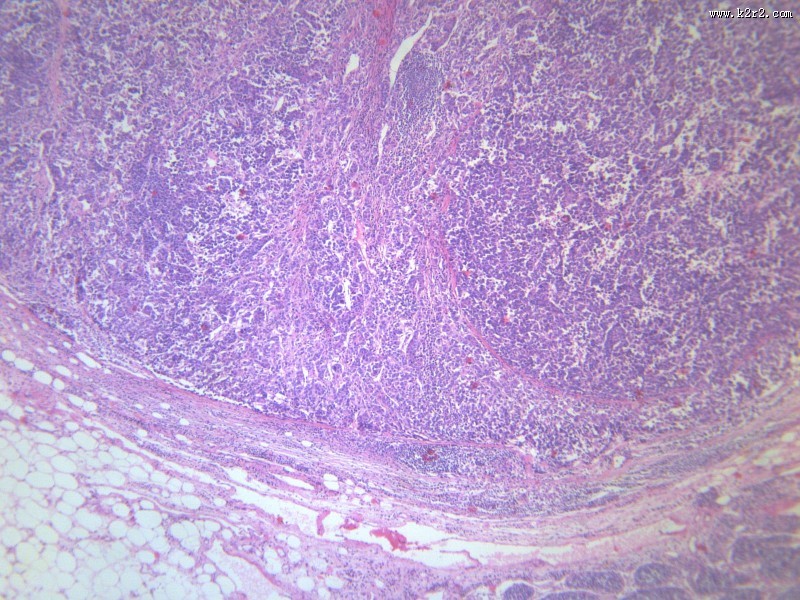

淋巴结内转移癌 - 第1张

淋巴结内转移癌

图集中 / 共有 12 张图片

腺癌肝转移大全

显微切片

癌症